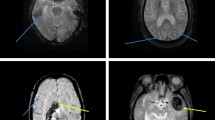

Graphical abstract

Role of MicroRNA associated with Alzheimer’s disease. Dysregulation of miRNA is associated with the formation and deposition of Amyloid-Beta Plaques as well as Neurofibrillary Tangles. Apart from this, it is also linked to impaired synaptic plasticity and increased expression of Beta-Amyloid Cleaving Enzyme 1(BACE1). All these eventually contribute to the progression of the disease.